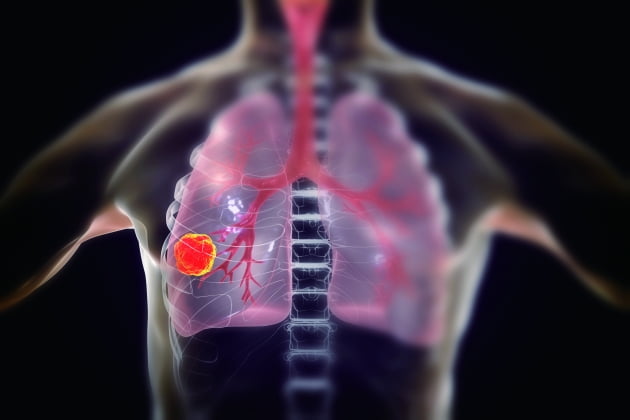

이러한 폐암의 원인으로 인해 폐암으로 진단되기 전에 폐암 초기증상을 조기에 발견하면 다른 장기로의 전이나 진행성 폐암으로의 진행을 어느 정도 지연시키거나 적절하게 치료할 수 있지만 일반적으로 폐암의 초기 단계는 특별한 징후나 증상이 없으므로 조기에 발견하는 경우는 극히 드뭅니다.

폐암 초기증상

잦은 기침

폐암 초기에는 기침이 잦거나 가래가 끓는 등 감기와 같은 증상이 나타날 수 있다. 따라서 폐암은 초기에 암인지 판단하기 어렵다. 또한 객담이나 적혈구를 동시에 토하는 것도 폐암을 진단하는 가장 중요한 증상 중 하나이다. 붉은 피가 섞인 가래 증상이 있으면 병원에 가서 검사를 받아야 한다.

또는 가래, 기침, 목소리가 쉬지 못하는 등 가벼운 감기라고 생각하여 폐암이 진행된 후에 종양이 발견되는 경우가 많습니다. 폐렴은 또한 기관지의 감염성 종양을 동반할 수 있습니다. 또한, 그럼에도 불구하고 폐렴만을 중심으로 치료를 하다 보면 상세한 검사 결과로 인해 종양을 식별하지 못하거나 폐암으로 발전할 수 있습니다.